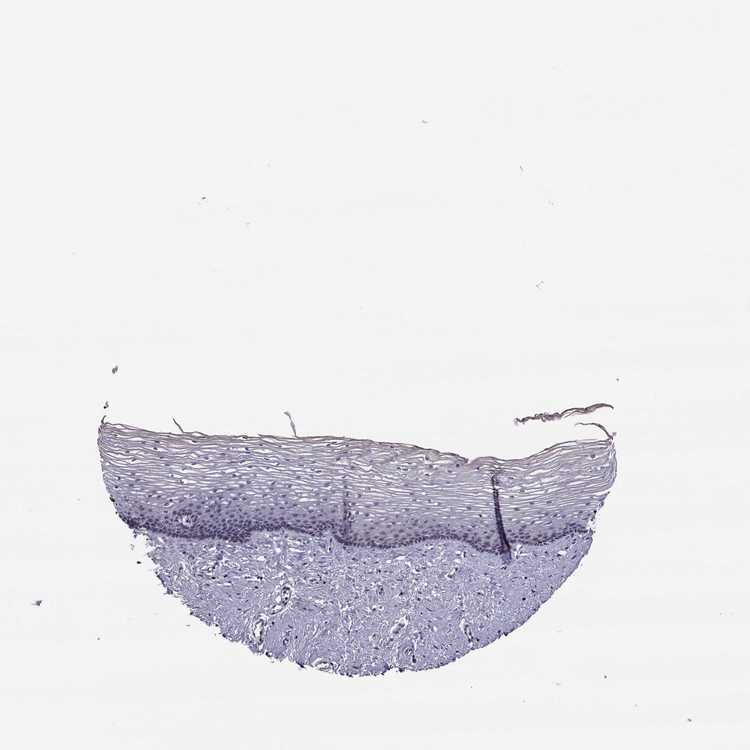

TISSUE PRIMARY DATA CERVIX Show tissue menu

CERVIX - Antibody stainingi

Antibody staining in the annotated cell types in the current human tissue is reported as not detected, low, medium, or high, based on conventional immunohistochemistry profiling in selected tissues. This score is based on the combination of the staining intensity and fraction of stained cells.

Each image is clickable and will lead to virtual microscopy that enables deeper exploration of all samples and also displays staining intensity scores, fraction scores and subcellular localization as well as patient and tissue information for each sample.

Antibody HPA032148Antibody HPA057356

Glandular cells LowLow

Squamous epithelial cells Not detectedNot detected